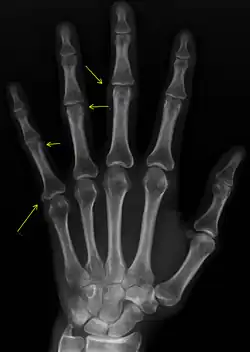

Sclerodactyly

Though it is the most easily recognizable manifestation, it is not prominent in all patients. Thickening generally only involves the skin of the fingers distal to the metacarpophalangeal joints in CREST. Early in the course of the disease, the skin may appear edematous and inflamed. Eventually, dermal fibroblasts overproduce extracellular matrix leading to increased tissue collagen deposition in the skin. Collagen cross-linking then causes a progressive skin tightening. Digital ischemic ulcers commonly form on the distal fingers in 30–50% of patients.[3]